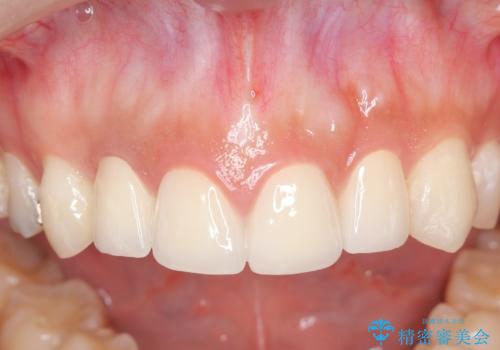

充填物の変色を繰り返す前歯のセラミック治療

- 神経をとった前歯の変色や、前歯の充填物の変色が大きくなってきたので審美性の改善を求めて来院されました。

充填物や充填物下に再発した虫歯を丁寧に除去し、セラミッククラウンによる審美性の改善、虫歯治療を計画します。

- 52.8万円(ジルコニアクラウン×4・仮歯×4)費用は治療当時の料金となります